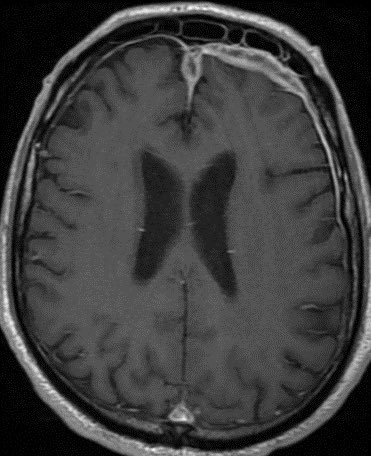

60 y/o with history of diabetes presents with progressive right proptosis, vision loss and confusion. What is the most likely diagnosis? 🧠

💡 Black Turbinate Sign has been reported as a finding highly suggestive of invasive fungal rhinosinusitis in immunocompromised patients

💡 Absent sinus mucosal enhancement is a 🔑 imaging feature as it implies invasion with vascular compromise and necrosis of the mucosa

The black turbinate sign is very specific in the appropriate setting though often not seen

💡 We must look for extra sinus invasion, particular intracranially, intraorbital, retromaxillary and other areas of absent mucosal enhancement to aid in the diagnosis